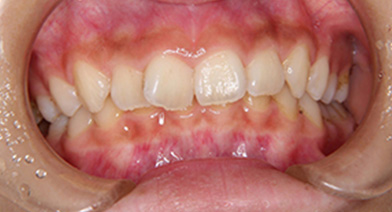

- 治療前 治療後

| 症例タイトル | 過蓋咬合 |

| 治療内容 | かみ合わせが深く、下顎が後方におしこめられているケースになります。 まず、バイトプレートによるかみ合わせの高さ、下顎の前方適応のコントロールをした後、ワイヤーを装着しました。 下顎の前方適応が難しいケースは、上顎の大臼歯の遠心移動が必要なこともあります。 |

| 患者さまの年齢 | 10代 |

| 患者さまの性別 | 女性 |

| 治療期間 | 1年4ヶ月 |